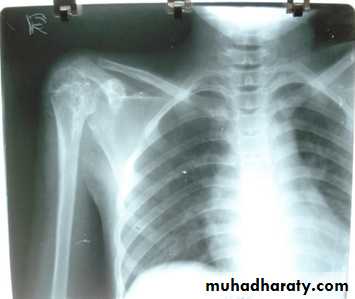

.Meniscal & ligamentous tears in the knee .

.Rotator cuff tears of the shoulder .